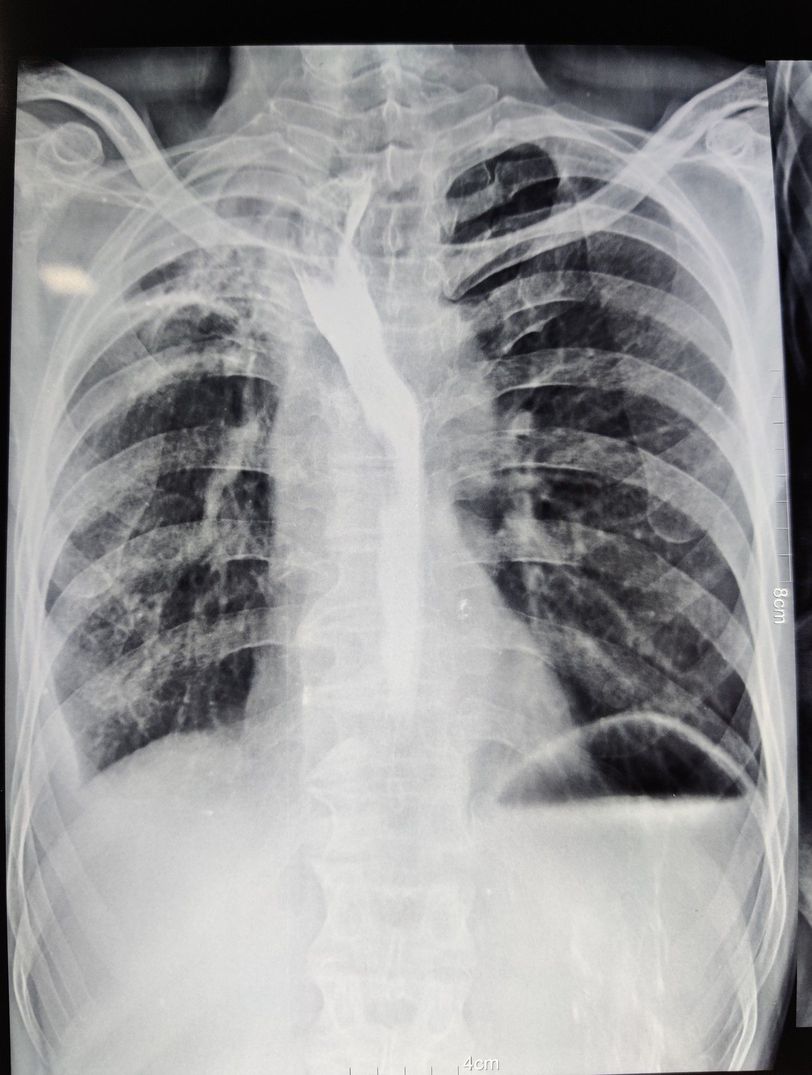

Only complaint is chronic diarrhoea

Oesophagus deviated towards right Obliteration of costopulmonary angle

Female? Any palpatory findings? CECT W/A? If female suspecting of ovarian CA if male then we have to rule out...